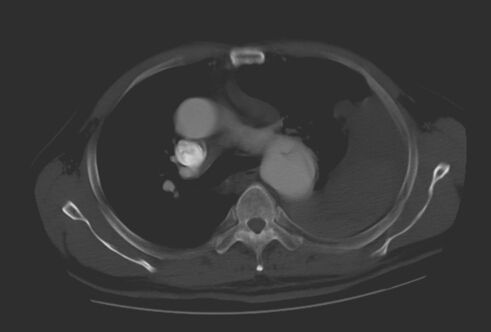

術前見主動脈夾層,胸腔大量積液和血凝塊